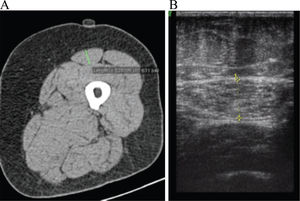

Evaluation of RFCSA using US and CT was performed by a single experienced examiner. RFCSA was measured by B-mode ultrasound on a Siemens Sonoline G40 (Korea, 2007) device using a 6-12 MHz linear transducer. The transducer was placed perpendicularly and transversely to the long axis of the thigh with excessive use of contact gel and minimum pressure to avoid muscle compression. RFCSA was measured at the midpoint between the anterior iliac spine and the upper lateral epicondyle of the femur. The measurements were performed on the dominant leg, with the patient in supine position, with legs extended and relaxed and toes pointing to the ceiling. The dominant leg was determined to be the leg used to climb the first rung of a ladder. A set of three measurements was taken, including one at the midpoint and the others 1 cm above and below this point. RFCSA was measured by placing the cursor on its inner edge, immediately below the external and internal muscle fascia in all patients (Figure 1).

Tomographic images were obtained using a Siemens Emotion device (Germany, 2007). RFCSA measurements were performed on the same leg and at the same point marked during the US evaluation, with the patient lying supine. The slices were 0.63 cm thick and were acquired 1 cm above and 1 cm below the predetermined midpoint with a low-radiation protocol (Figure 1). The CT measurement data sets were analyzed in a blinded and randomized manner.